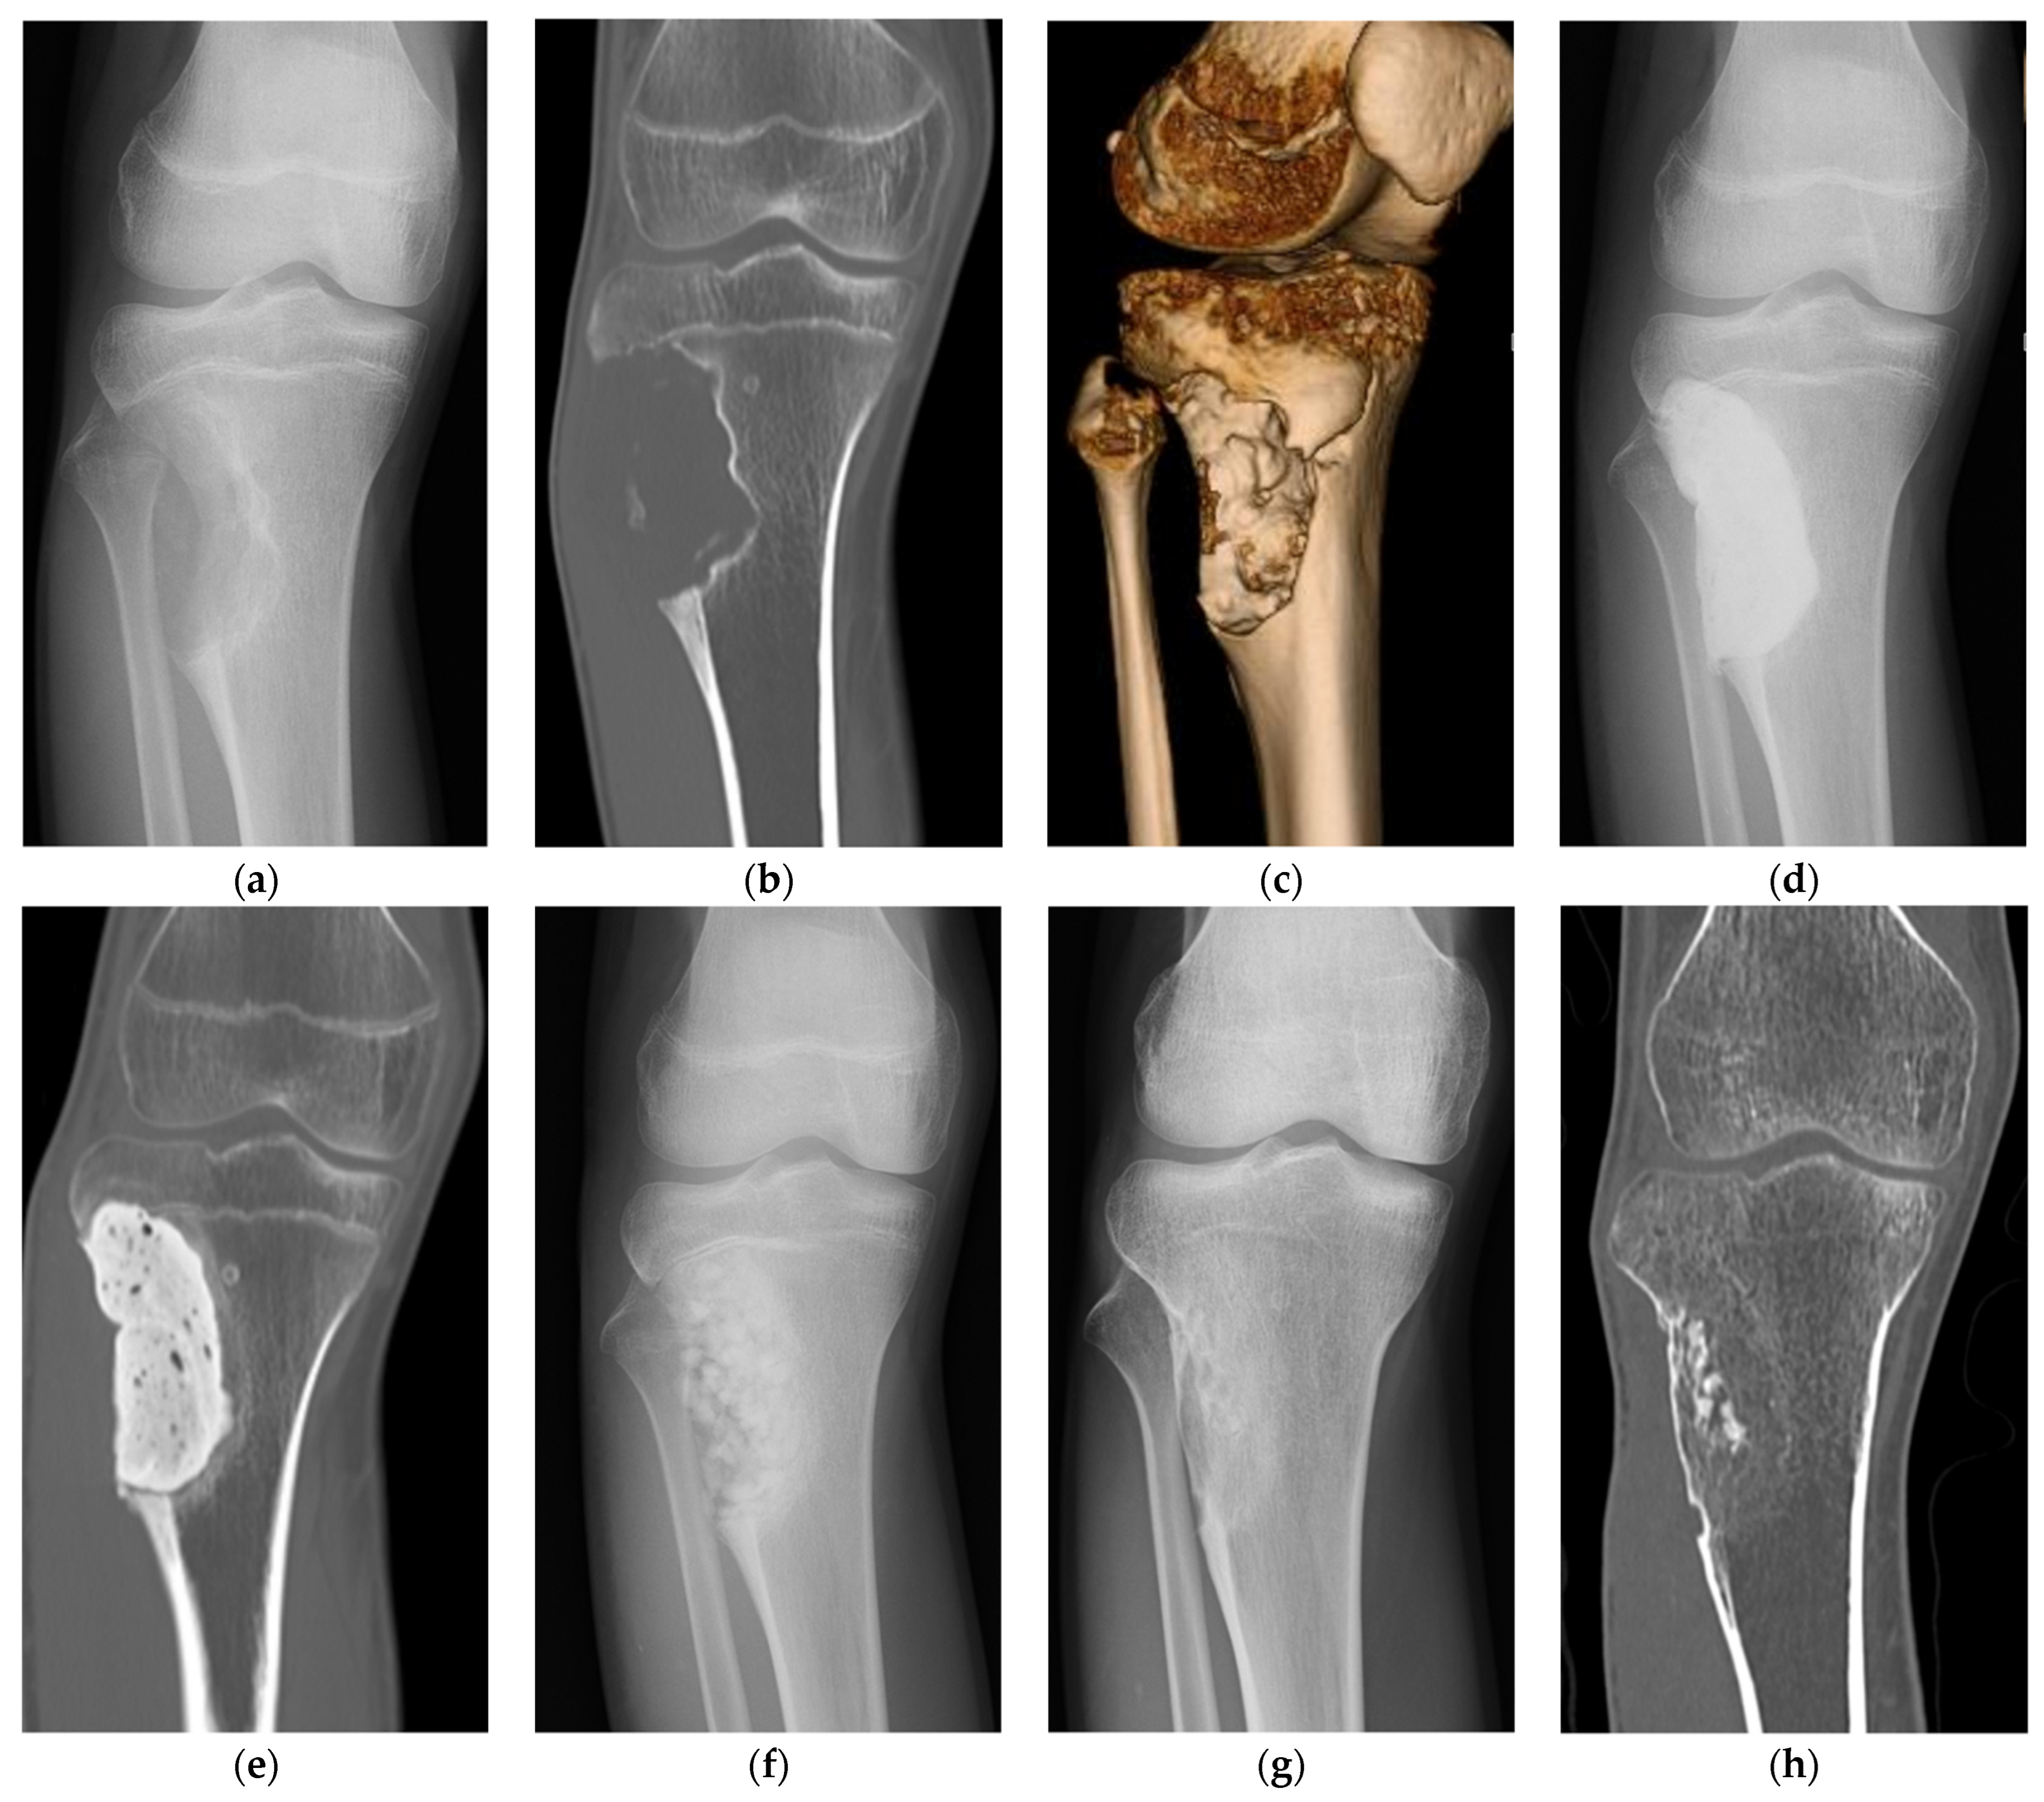

- Tanaka, T.; Kumagae, Y.; Saito, M.; Chazono, M.; Komaki, H.; Kikuchi, T.; Kitasato, S.; Marumo, K. Bone formation and resorption in patients after implantation of beta-tricalcium phosphate blocks with 60% and 75% porosity in opening-wedge high tibial osteotomy. J. Biomed. Mater. Res. B Appl. Biomater. 2008, 86, 453–459. [Google Scholar] [CrossRef]